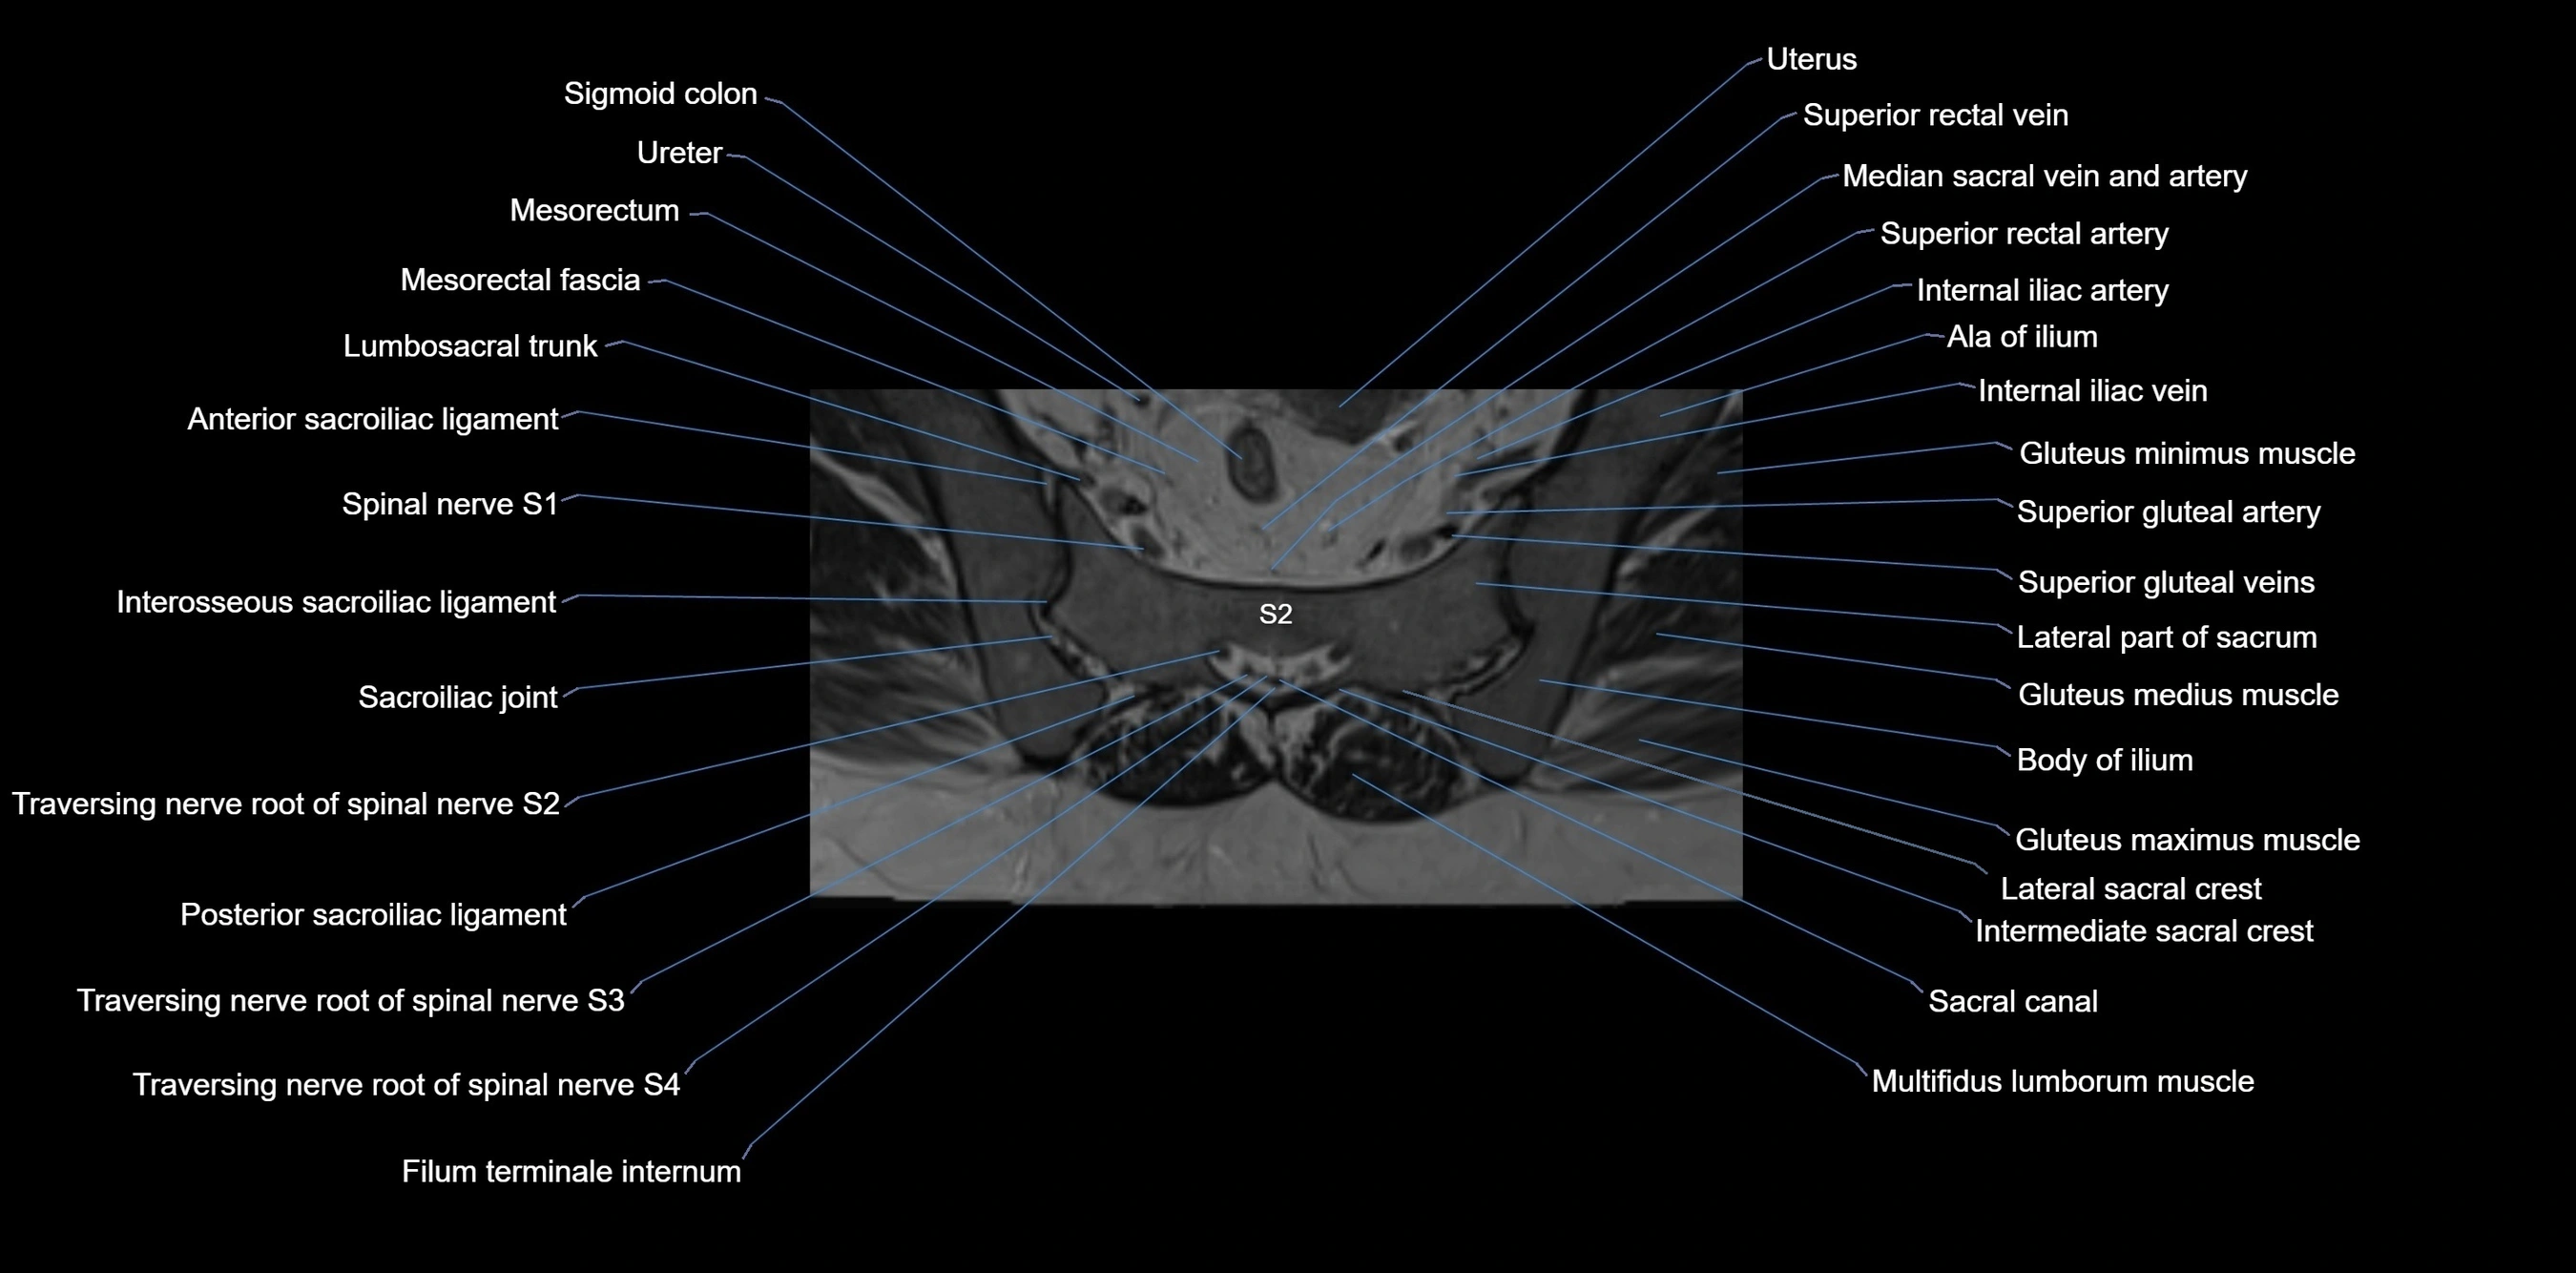

MRI image

image